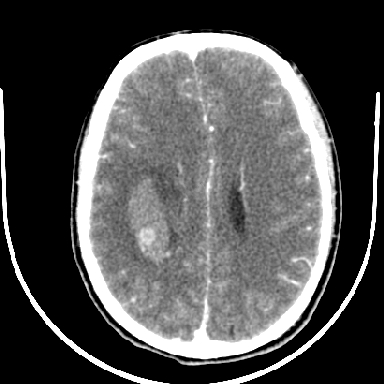

考虑高血压性脑出血,依据:

1是高血压性脑出血的好发部位,形态呈肾形,是高血压性脑出血的常见形状

2增强时占位效应加重了,考虑出血还没有停止

3病灶周围水肿不是太厉害,一般肿瘤出血水肿多非常明显

4病灶周围的‘软组织’影没有明显的强化

5至于脑血管畸形引起的出血,暂时没有看到明显的畸形血管影,也不太支持

支持右侧基底节区(主要为外囊区)原发性脑出血。

支持右侧基底节区(主要为外囊区)原发性脑出血----有无血管畸形及动脉瘤或说出血原因待查